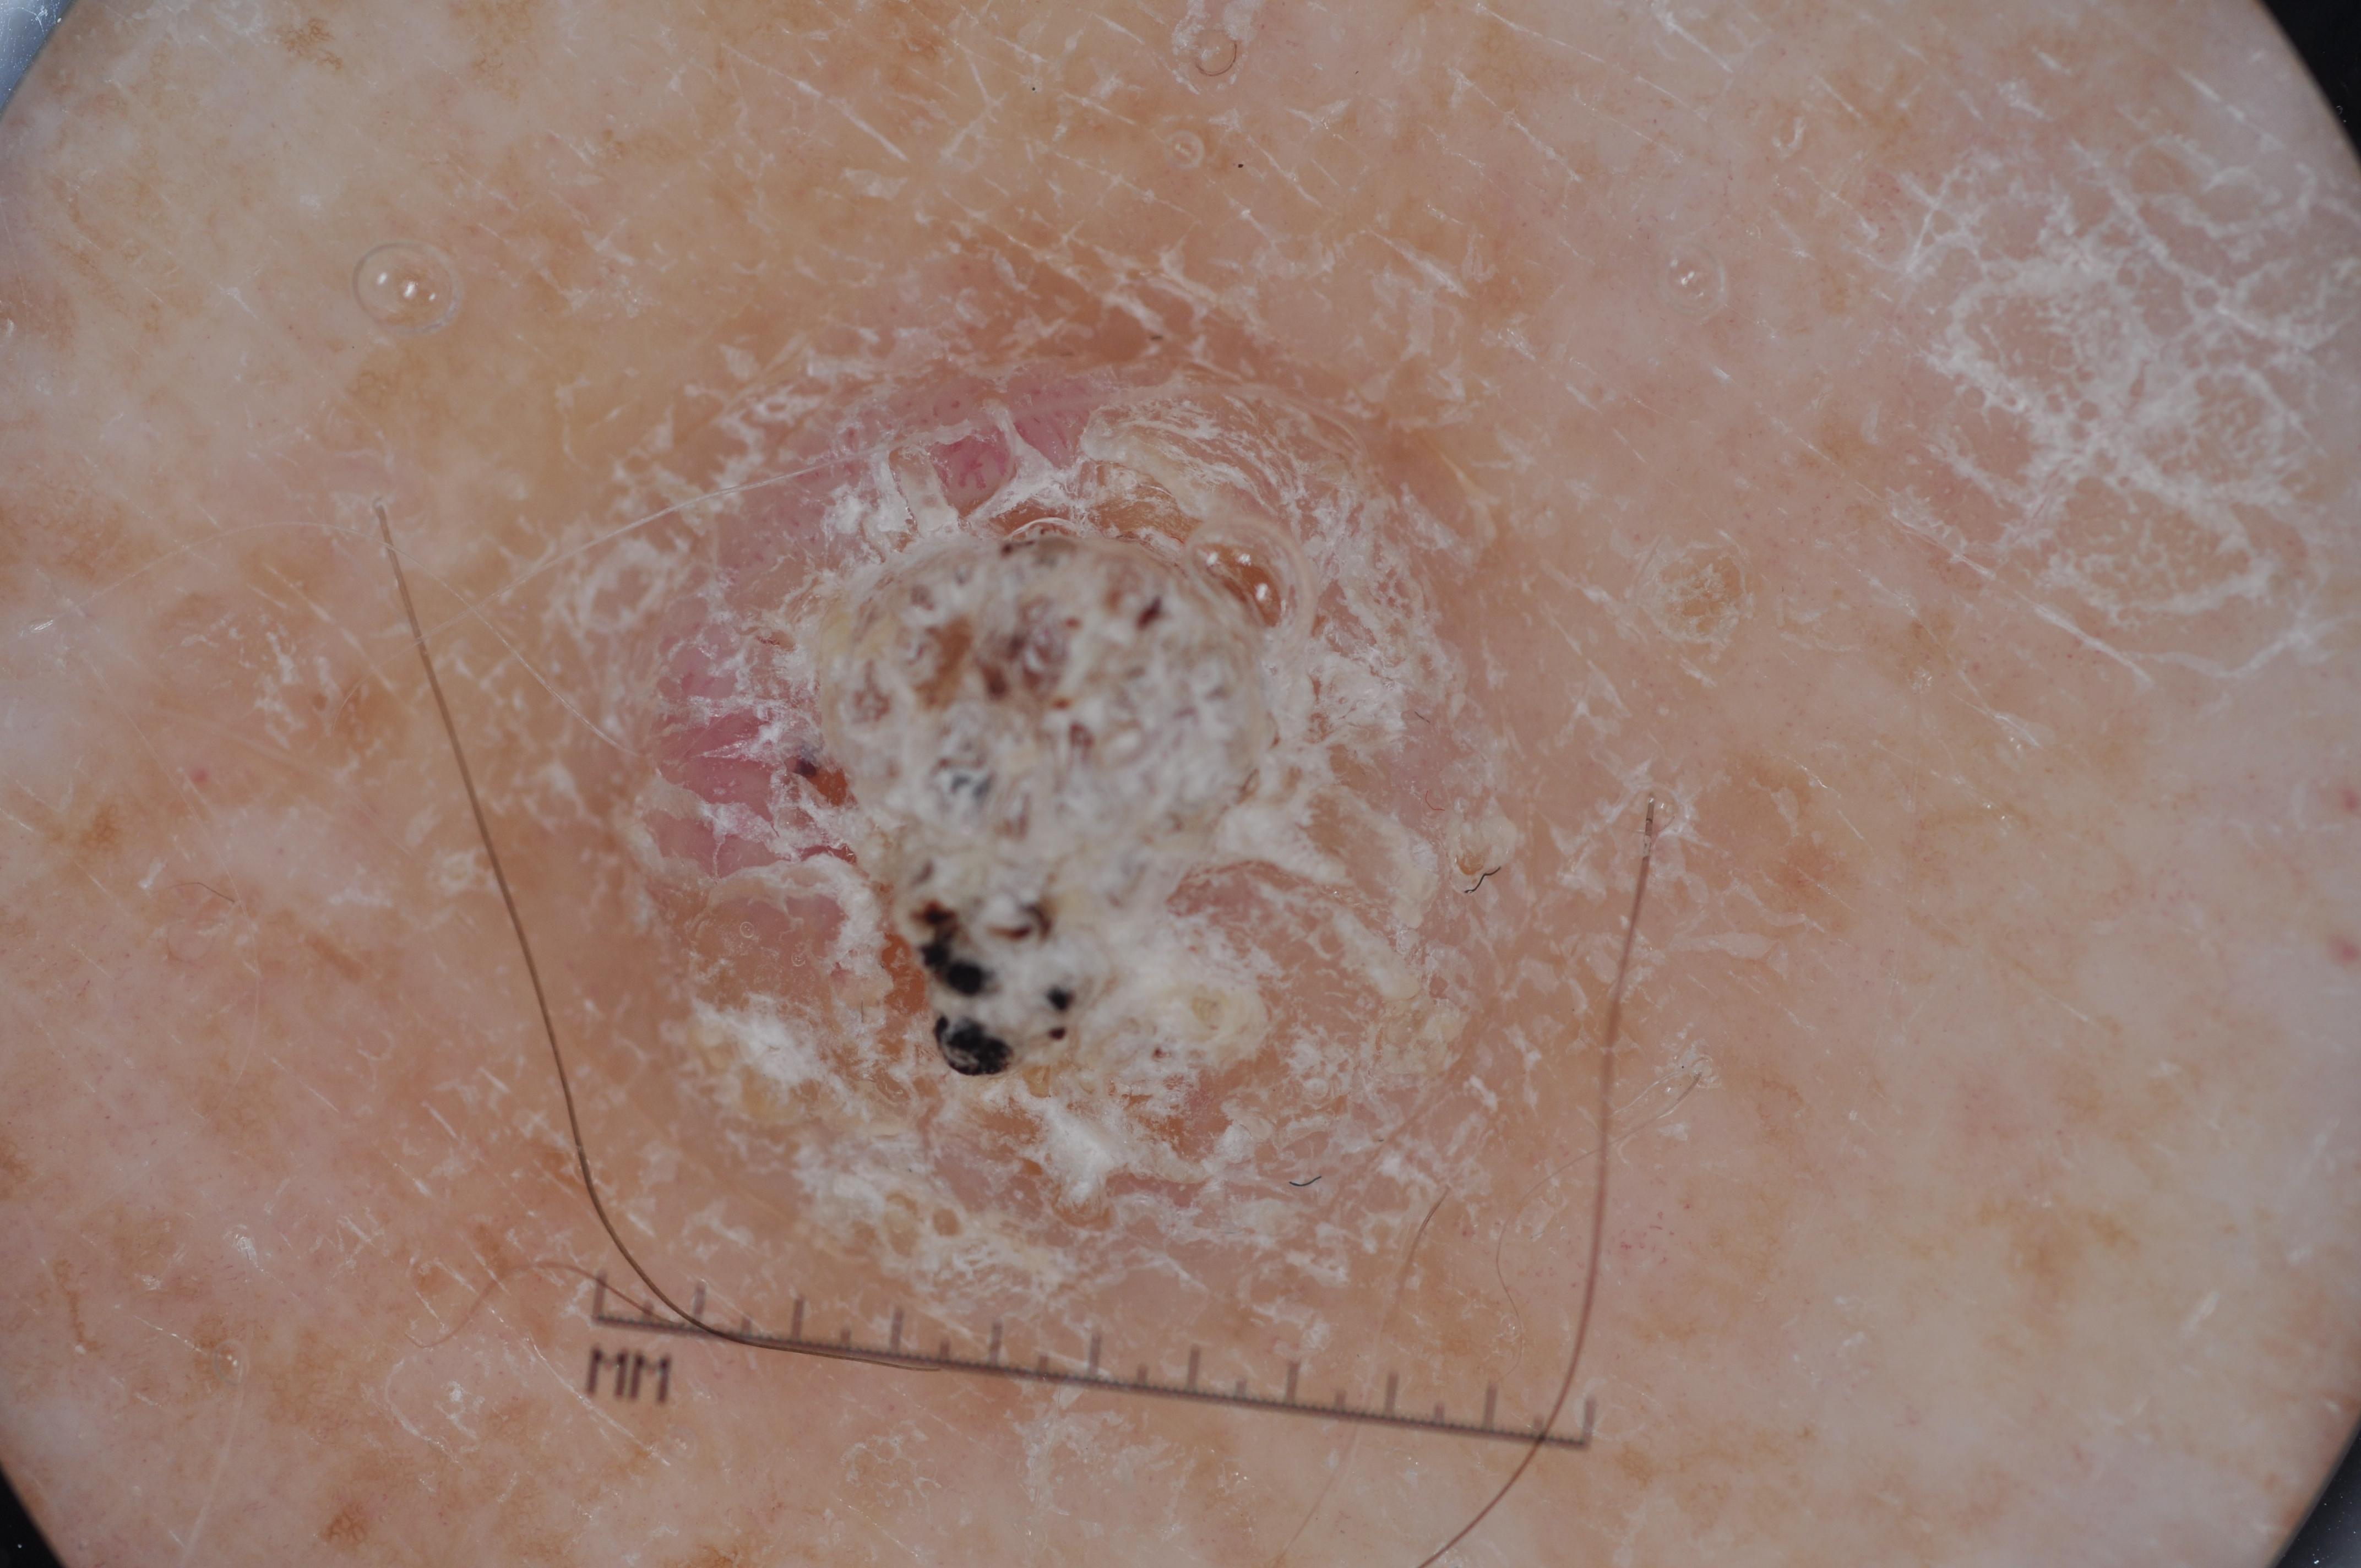

ISIC-DICM-17K (ISIC Dermoscopic Images and Clinical Metadata 17K) is a curated and balanced dataset derived from the International Skin Imaging Collaboration (ISIC) Archive Gallery. It comprises 17,060 dermoscopic images and clinical metadata (8,530 melanoma and 8,530 non-melanoma classes).

For more details, please follow the project’s GitHub repository: https://github.com/mmu-dermatology-research/isic-dicm-17k

This dataset was used in this study and benchmark to explore the effectiveness of multimodal learning for skin lesion classification:

S. Ahammed, X. Cui, W. Lu and M. H. Yap, "Skin Lesion Classification using Dermoscopic Images and Clinical Metadata: Insights from Multimodal Models," 2025 IEEE/CVF Conference on Computer Vision and Pattern Recognition Workshops (CVPRW), Nashville, TN, USA, 2025, pp. 222-230, DOI: 10.1109/CVPRW67362.2025.00027